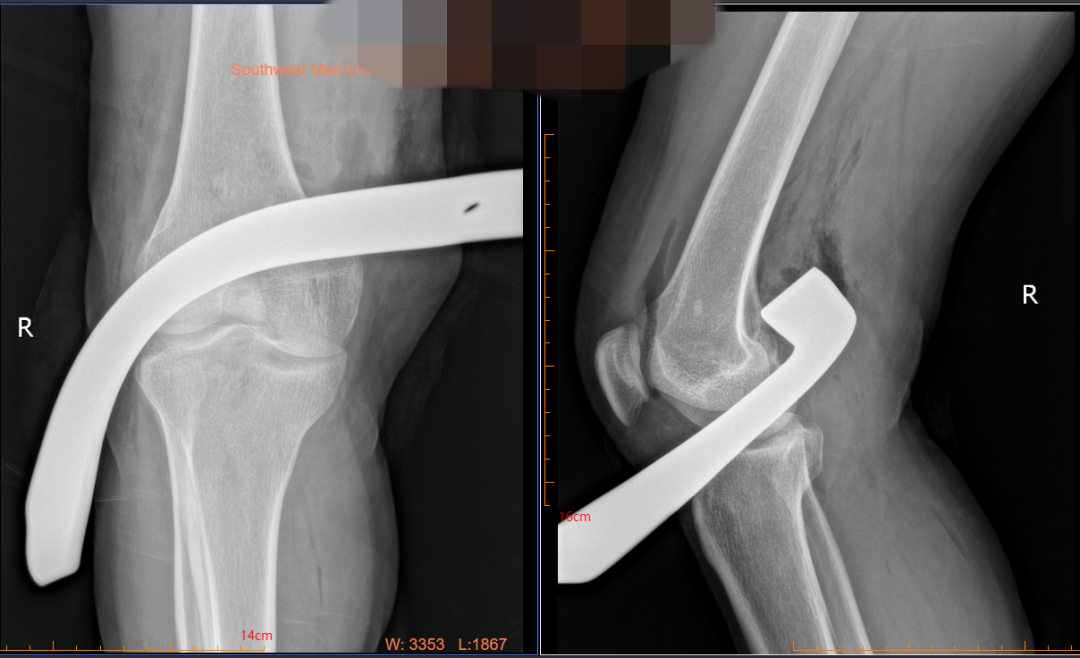

3月16日下午两点半左右,一声惨叫响彻农田。正在田地里使用旋耕机犁地的魏女士不慎被旋耕机绞伤右腿,疼得直叫唤,同在旁边农作的家属见状赶紧放下锄头上前查看。只见魏女士右腿鲜血直流,上面还插着一块刀片,家属赶紧拨打了119和120。

消防队员现场紧急拆除旋耕机后,医护人员立即予以包扎止血等处理,随后送至西南医科大学附属中医医院急诊科。急诊科以“右下肢贯通伤伴血管损伤”收入骨伤科手外·儿骨·烧伤整形组。

刘安铭副教授接诊发现:魏女士整个右下肢被严重绞伤,刀片从右膝内侧经腘窝贯通至小腿近段外侧,血肉模糊、伤口被大量泥沙污染,肢体冰凉,供血较差。

16日20:30,手术开始。因旋耕机刀片贯穿右腿,切断了右腿动脉,出血量大,同时挫伤了神经,加上魏女士伤口覆盖了大量泥沙,给手术带来了诸多困难。

经过科室团队通宵奋战,17日05:30手术结束,成功取出了一块约30cm长的旋耕机刀片,由于血管缺损,切取对侧大隐静脉进行血管桥接,恢复了右下肢血液流通,保住了右腿。